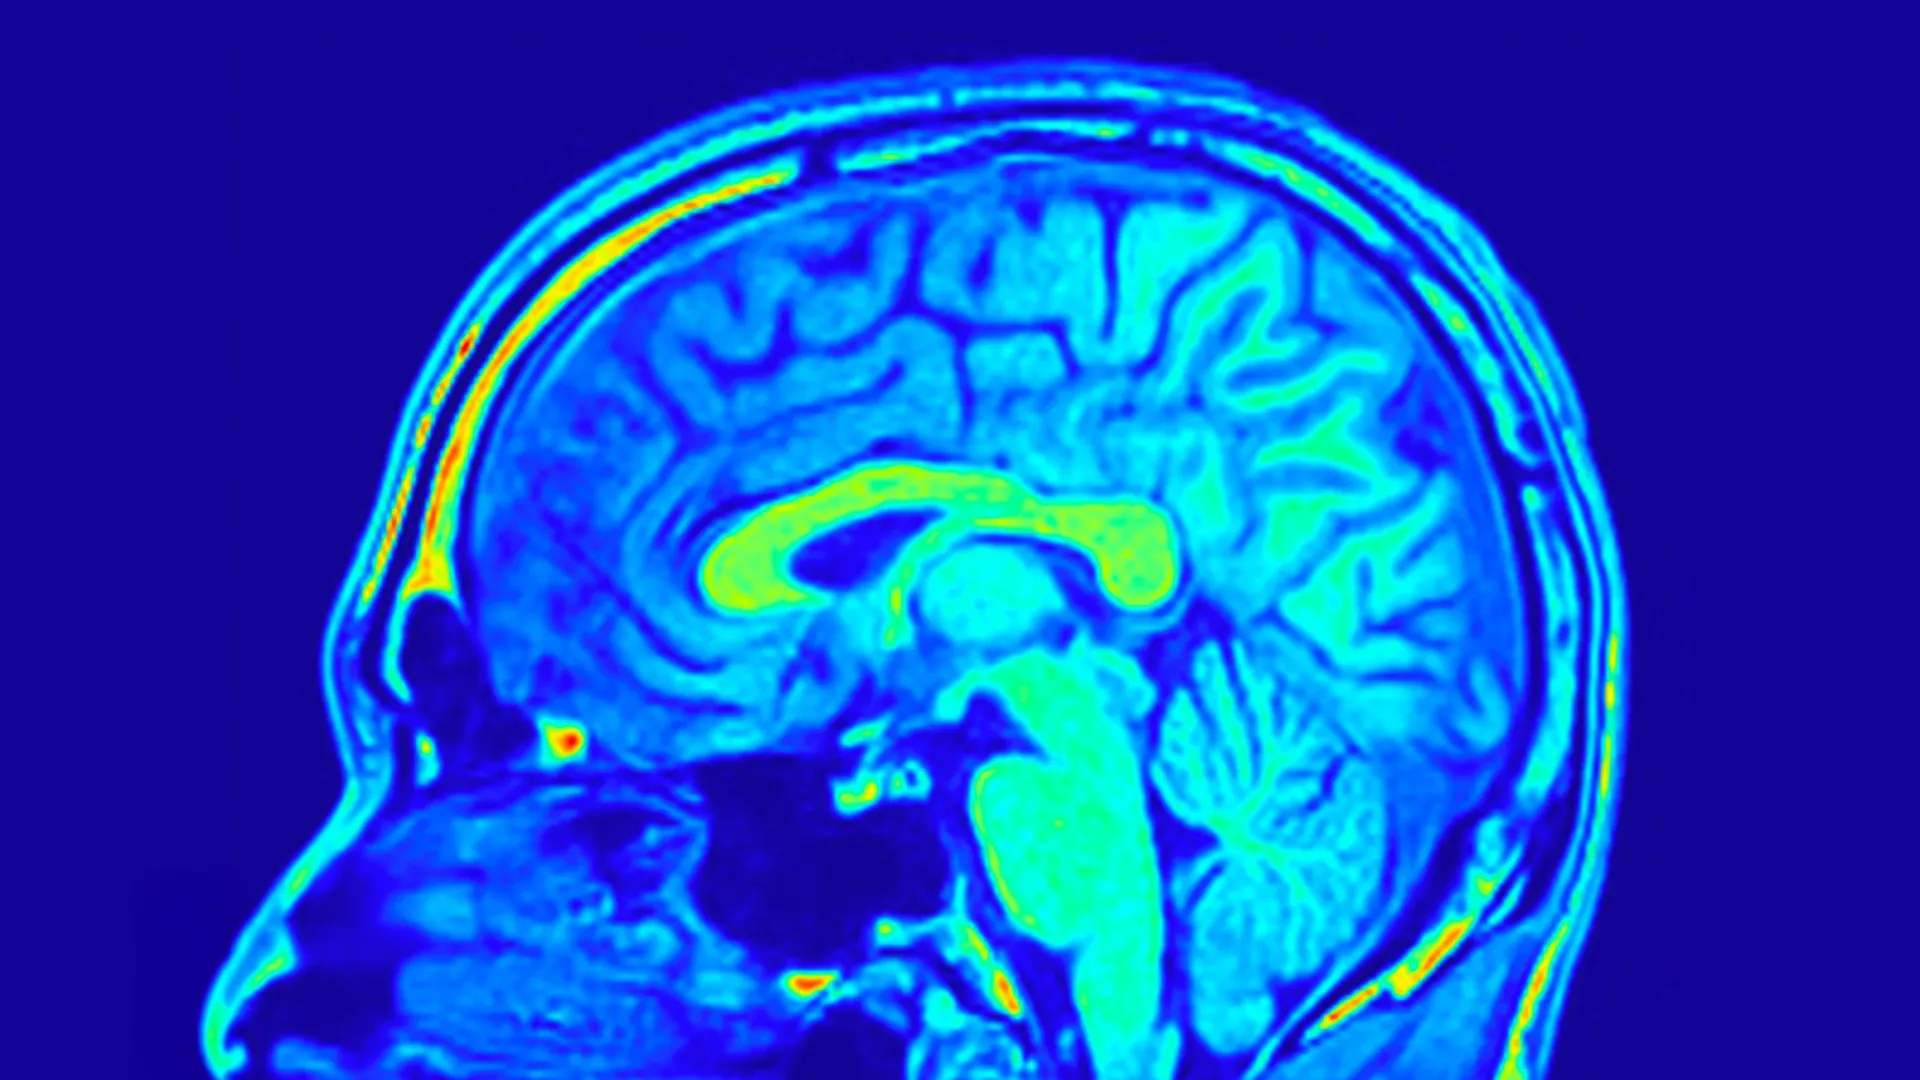

To comprehensively assess treatment outcomes, the research team employed the widely validated 24-item Hamilton Depression Scale (HAMD-24), a standardized clinical questionnaire, to quantify the severity of depressive symptoms. In parallel, biological data was meticulously collected, including peripheral blood samples and magnetic resonance imaging (MRI) brain scans, with the explicit aim of discerning alterations in brain structure and underlying biological processes.

The neuroimaging data provided even more profound and nuanced insights into the differential effects of the treatments. The researchers identified that distinct neural networks, comprising interconnected brain structures, possessed the capacity to prognosticate changes in depression scores within both treatment groups. These networks serve as a functional representation of how different brain regions are organized and communicate with each other.

Of particular significance was the observation that certain brain patterns demonstrated predictive power exclusively in individuals undergoing treatment with Yueju Pill. These predictive patterns were derived from measurements of sulcus depth and cortical thickness, parameters that delineate the intricate folding of the brain’s surface and the depth of its outermost layer, respectively. Both of these anatomical features are intrinsically linked to neurodevelopment and functional integrity. Further granular analysis indicated that the brain’s visual processing network played a particularly pivotal role in forecasting improvements in both depressive symptoms and BDNF levels among those administered Yueju Pill.

These converging findings strongly suggest that the identification of specific brain network configurations through MRI scans could serve as a powerful predictive biomarker for assessing individual patient responses to Yueju Pill therapy in the context of MDD. This innovative approach transcends the limitations of symptom-based diagnostic strategies, ushering in an era of more personalized and targeted antidepressant interventions.